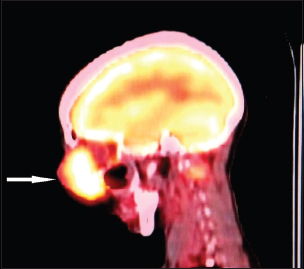

A 50-year-old female with no known comorbidities presented with epiphora left eye, blood in tears, and swelling over left lacrimal sac site of 2 months' duration. Clinical examination revealed a large, erythematous, lobulated 8 cm × 5 cm firm swelling fixed to underlying structures extending from left medial canthus to lower cheek area and left alae of nose covering the entire left eye with resultant restricted eye opening and no perception of light [Figure 1]. Right eye was normal with a visual acuity of 6/12. Computed tomography (CT) scan face and neck showed a 6.5 cm × 5.8 cm × 5.3 cm mass lesion left pre-orbital region eroding the medial wall of left maxillary sinus, left nasal cavity, nasal septum, anterior ethmoidal sinus and left orbit. No intracranial extension was seen. Multiple lymph nodes were seen at Level II and III [Figure 2]. Whole body positron emission tomography scan showed a localized disease without systemic dissemination [Figure 3].

| Figure 3 Positron emission tomography scan showing an exophytic ill-marginated soft-tissue lesion anteromedial to left eyeball without any intracranial extension (white pointer)